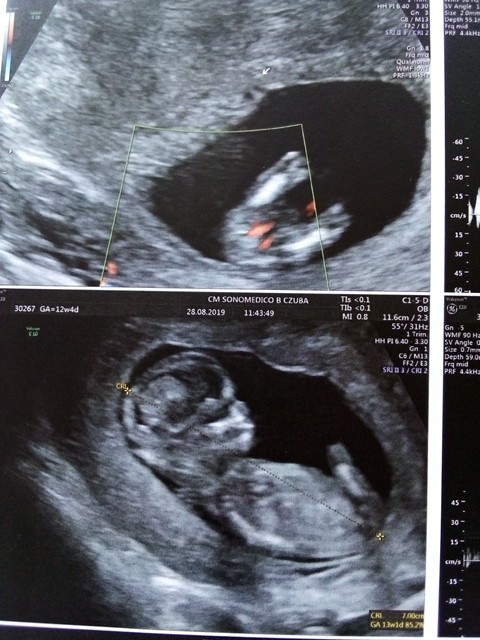

Z tego co widac na usg jest 12 tydzien. Jeszcze za wczesnie moze zeby ustalic plec..

W 12 tyg. Nub wygląda niemal identycznie u obu płci, tylko kąt nachylenia świadczy o tym czy to chłopiec, czy dziewczynka. Przy czym w 12 tyg.Może jeszcze zmienić się kąt nachylenia. Ja tak miałam. Lekarz na 200% mówił córeczka, potwierdził jeszcze w 22 tyg. dziewczynkę a urodził się zdrowy piękny syneczek. Pewność masz dopiero po porodzie. :)